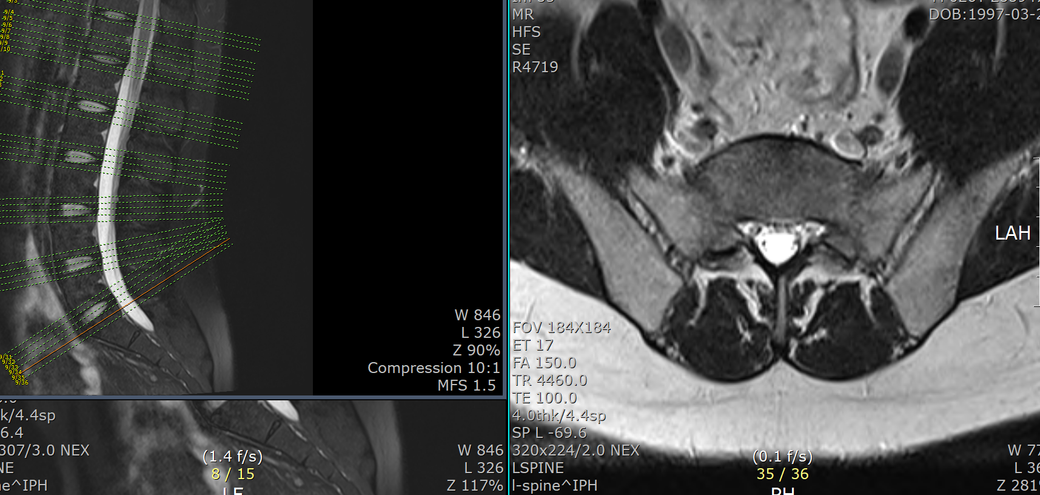

T12-L1 level에서 disc가 뒤쪽 Lt. central aspect로 protrusion되어 있고 mild한 dural sac indentation을 주고 있음.

• 3번 째 사진

아래 사진에 있는 부위가 아마 T12/L1 사이에 디스크가 살짝 뒤로 빠져있다는 부위이실겁니다.

옆에서 보면 두번째 사진이구요.

우선은 이 디스크 내장증으로 인한 연관통으로 보고 요추전만 자세를 잘 실천해보시는게 가장 우선 필요한 조치이겠습니다.

수술을 주로 다루는 신경외과, 정형외과 선생님들의 경우에 심한 디스크탈출 및 신경뿌리를 누르는 신경뿌리병증이 생길만한 병변만 통증을 유발한다고 보시기 때문에 문제될만한 병변이 없다고 이야기 하셨을텐데 저렇게 작게 찢어진 디스크 때문에도 충분히 통증이 생길 수 있습니다. 물론 찢어진 디스크의 위치에 비해 통증이 밑에 있는 편이시지만 이게 불가능한건 아닙니다. 디스크 내장증이라고 하며 이럴때는 요추전만 자세가 가장 중요합니다.

피부가 찢어지면 봉합을 하듯이 찢어진 부위가 아물도록 상처를 오므려놓는게 필요한데 이게 바로 요추전만 자세의 유지입니다.

허리를 하루에 한번도 안굽힌다고 생각하고 생활해보시기 바랍니다.

머리도 서서 샤워하면서 감으셔야합니다. 아마 1달 이내에 통증이 많이 줄어드는걸 느끼실 수 있을겁니다.